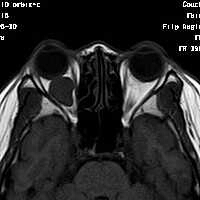

女,54岁,头痛头晕月余,无眼部症状及视力异常。 影像表现:右侧眼球后方占位病变,考虑海绵状血管瘤可能性大,鉴别:视神经鞘瘤、脑膜瘤及炎性假瘤。 病例点评:眼眶内血管瘤是较常见的良性肿瘤,其中以海绵状血管瘤最常见。可发生于任何年龄,主要表现为眼球突出及偏位,在低头或哭泣时可有突眼加重。可经眶缘触及具有压缩性的肿块。视力损害多较缓慢。肿块大多位于肌锥内,其次为肌锥外,平扫呈边界清楚的圆形、卵圆形或分叶状肿块,增强扫描呈缓慢进行性显著强化为其特征性表现。